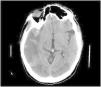

This is the case of a 47-yearl old man with a past medical history of native mitral aortic valve acute endocarditis who required valvular repair and supracoronary tube implantation. The patient is admitted to the ICU after a scheduled reintervention due to severe paravalvular leak followed by valvular replacement with mechanical prosthesis. Initially extubated and without neurologic focality. A few minutes after experiencing the early seizure the patient requires orotracheal intubation. The emergency cranial CT scan performed (Fig. 1) reveals the presence of air into the right middle cerebral artery territory, M2 (blue arrow [the color of the figure can only be seen on the electronic version]) and part of its cortical branches, as well as air bubbles into the left posterior cerebral artery (x) that consistent with gas embolism. The radiographic follow-up performed 48 h later (Fig. 2) reveals the presence of an extensive established right parietal-temporal-occipital and left occipital ischemic infarction with slight midline deviation.